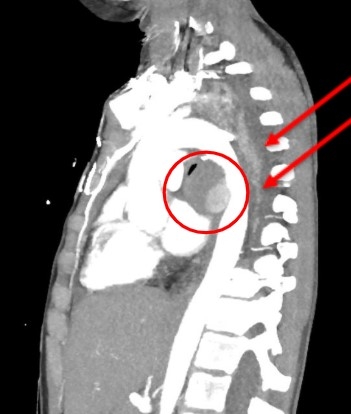

A 9-year-old female with a history of MRSA bacteremia three months ago presented to an outside hospital due to respiratory distress with concerns for pneumonia versus atelectasis. She was transferred to our hospital for escalation of care. On arrival, she had severe left-sided back pain and shortness of breath. Chest x-ray showed complete atelectasis of the left lung (Image 1). Chest CT scan revealed occlusion of the left mainstem bronchus with left mediastinal shift. Echocardiogram was normal. Atelectasis did not improve despite pulmonary clearance regimen (chest physiotherapy, albuterol, hypertonic saline). Reassessment via Chest CT scan revealed a large mycotic pseudoaneurysm that appeared to have a thrombus located in the descending aorta, compressing the left main bronchus and causing atelectasis on the left lung with mediastinal shift (Image 2).